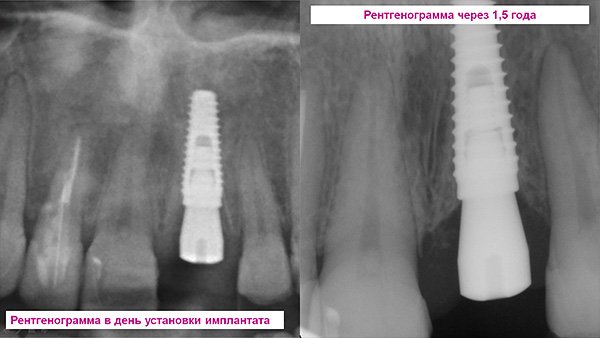

Agora vamos ver como tudo isso pode parecer na prática - daqui em diante, como exemplo, é apresentado um caso clínico de próteses dentárias anteriores em um implante Snucone.

Esta é a situação inicial: a coroa do dente está quebrada quase sob a raiz:

A remoção mais não traumática da raiz com a preservação das gengivas e paredes ósseas do buraco é realizada:

Em seguida, o retalho gengival é cortado e reclinado, um implante é inserido no orifício e o material ósseo granular é introduzido para a regeneração óssea:

Em seguida, a ponta da gengiva retorna ao seu lugar e é fixada com uma sutura:

É assim que um pilar individual feito de zircônia montado em um implante se parece com:

O resultado final das próteses usando uma coroa totalmente em cerâmica: